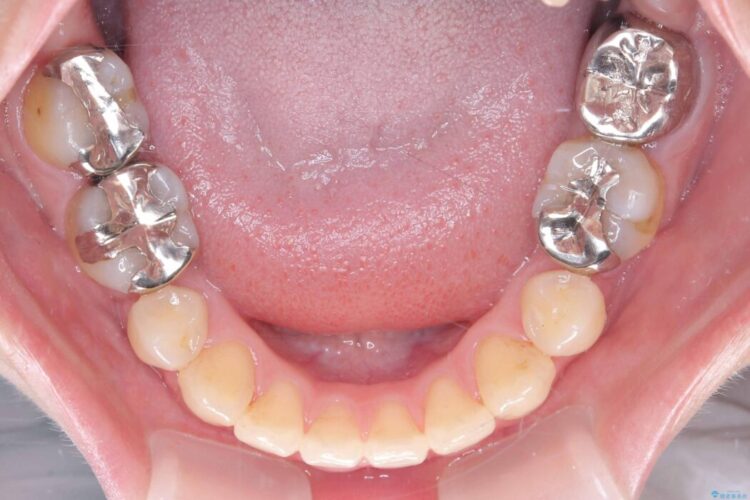

精密検査の結果、上顎左右4番および下顎左右5番の計4本を抜歯し、目立ちにくいクリア装置にて治療を行いました。

気になっていたガタつきや開咬が改善され、見た目だけでなく咬み合わせの機能面も大きく向上し、大変ご満足いただけました。